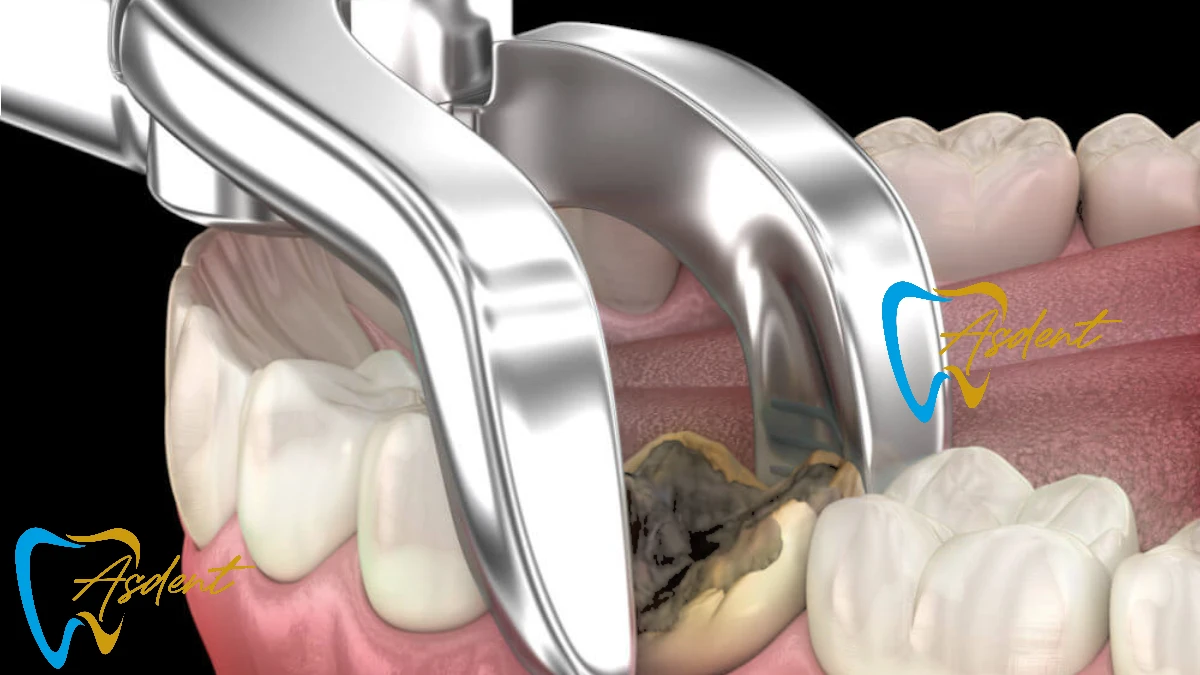

Diş çekimi, bir dişin kemik yuvasından çıkarılması işlemidir. Bu prosedür, bir diş ciddi şekilde hasar gördüğünde, çürüdüğünde veya başka diş problemlerine neden olduğunda genellikle gereklidir. ASDENT Diş Polikliniğinde hem basit çekimler (görünür dişler için) hem de cerrahi çekimler (gömülü veya kırık dişler için) gerçekleştiriyoruz.

- Şiddetli Diş Çürüğü: Bir diş dolgu veya kuron ile kurtarılamayacak kadar hasar gördüğünde.

Basit çekimlerde diş yavaşça gevşetilir ve çıkarılır. Cerrahi çekimlerde veya ağız cerrahisinde, dişe veya etkilenen bölgeye ulaşmak için küçük bir kesi yapılabilir. - Adım 4: Sonrası Bakım Talimatları